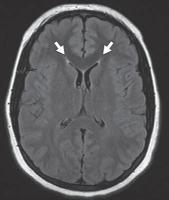

图 5A——小血管缺血性疾病。半卵圆中心水平的平扫 CT 图像显示弥漫性皮质下白质低密度以及代表腔隙的更多局灶性低密度(箭头)

图 5B —小血管缺血性疾病。FLAIR 图像显示多个脑室周围高信号灶。

在 CT 上,小血管缺血性疾病表现为小穿支动脉区域皮质下和脑室周围白质的多发性白质低密度影。基底神经节和幕上区域也可见局灶性腔隙(图 5A )。高血压患者常见的自发性出血,一般位于基底节或丘脑。在存在败血症或先天性心脏病的情况下,栓子也会在血管区域之间的边界处产生分水岭梗塞。MRI 显示缺血区域在 T2/FLAIR呈现 高信号(图 5B ))。扩散受限存在于急性期,但在亚急性期和慢性期正常化。

其他微血管病大脑受累的分布不同。在淀粉样血管病中,多灶性和脑叶出血性中风很常见。GRE/磁敏感加权成像可用于检测隐匿性微出血病灶(图6A 、 6B, 和6C)。